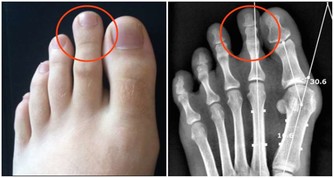

一個很明顯的信號能夠驗證,人的足部有一個明顯能摸到脈息的方位,即是足背正中最高點,輕摸能感遭到脈動。假如是輕度下肢動脈阻塞的人來說,能摸到足部脈息,證實動脈血一向通到足背部。可走了一段路後,再摸,就摸不到脈息了,這時,很可能發作了動脈血管阻塞。

自查血管阻塞辦法

把腳舉高,45度,2分鐘,仔細觀察兩條腿。假如一條腿呈蒼白,乃至是蠟白,腿部肌膚出現透明狀,待腿拿下來後,康復正常坐姿,假如這條腿出現微紅,這就闡明這條腿現已缺血了。